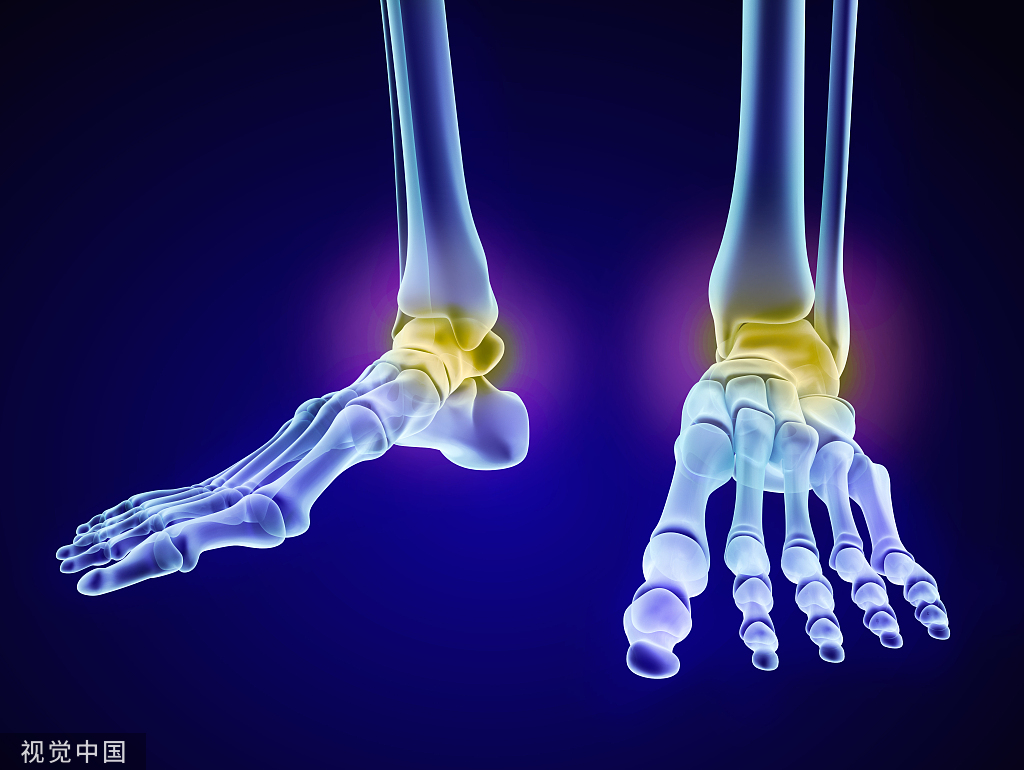

膝关节解剖

病因和发病机制关节的基本结构:关节面、关节软骨、关节腔、关节囊关节软骨:厚度约为2-7mm软骨表面光滑,摩擦系数很小,故有利于关节活动。